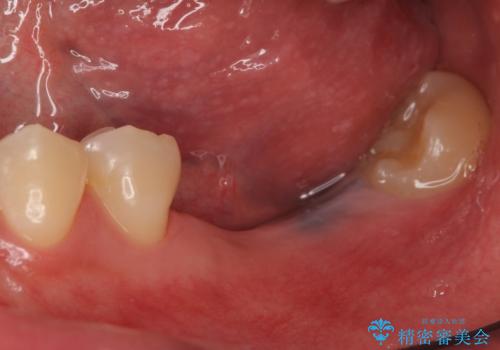

オールセラミッククラウンについて

今回用いたオールセラミッククラウンはジルコニアフレームという白い素材の上にセラミックを盛っているため、審美性が非常に高いのが特徴です。

また、ジルコニアは人工ダイヤモンドの材料にも使われているほど高い強度を持っており、そのためオールセラミッククラウンは審美性だけでなく、奥歯やブリッジの補綴も可能とするクラウンです。